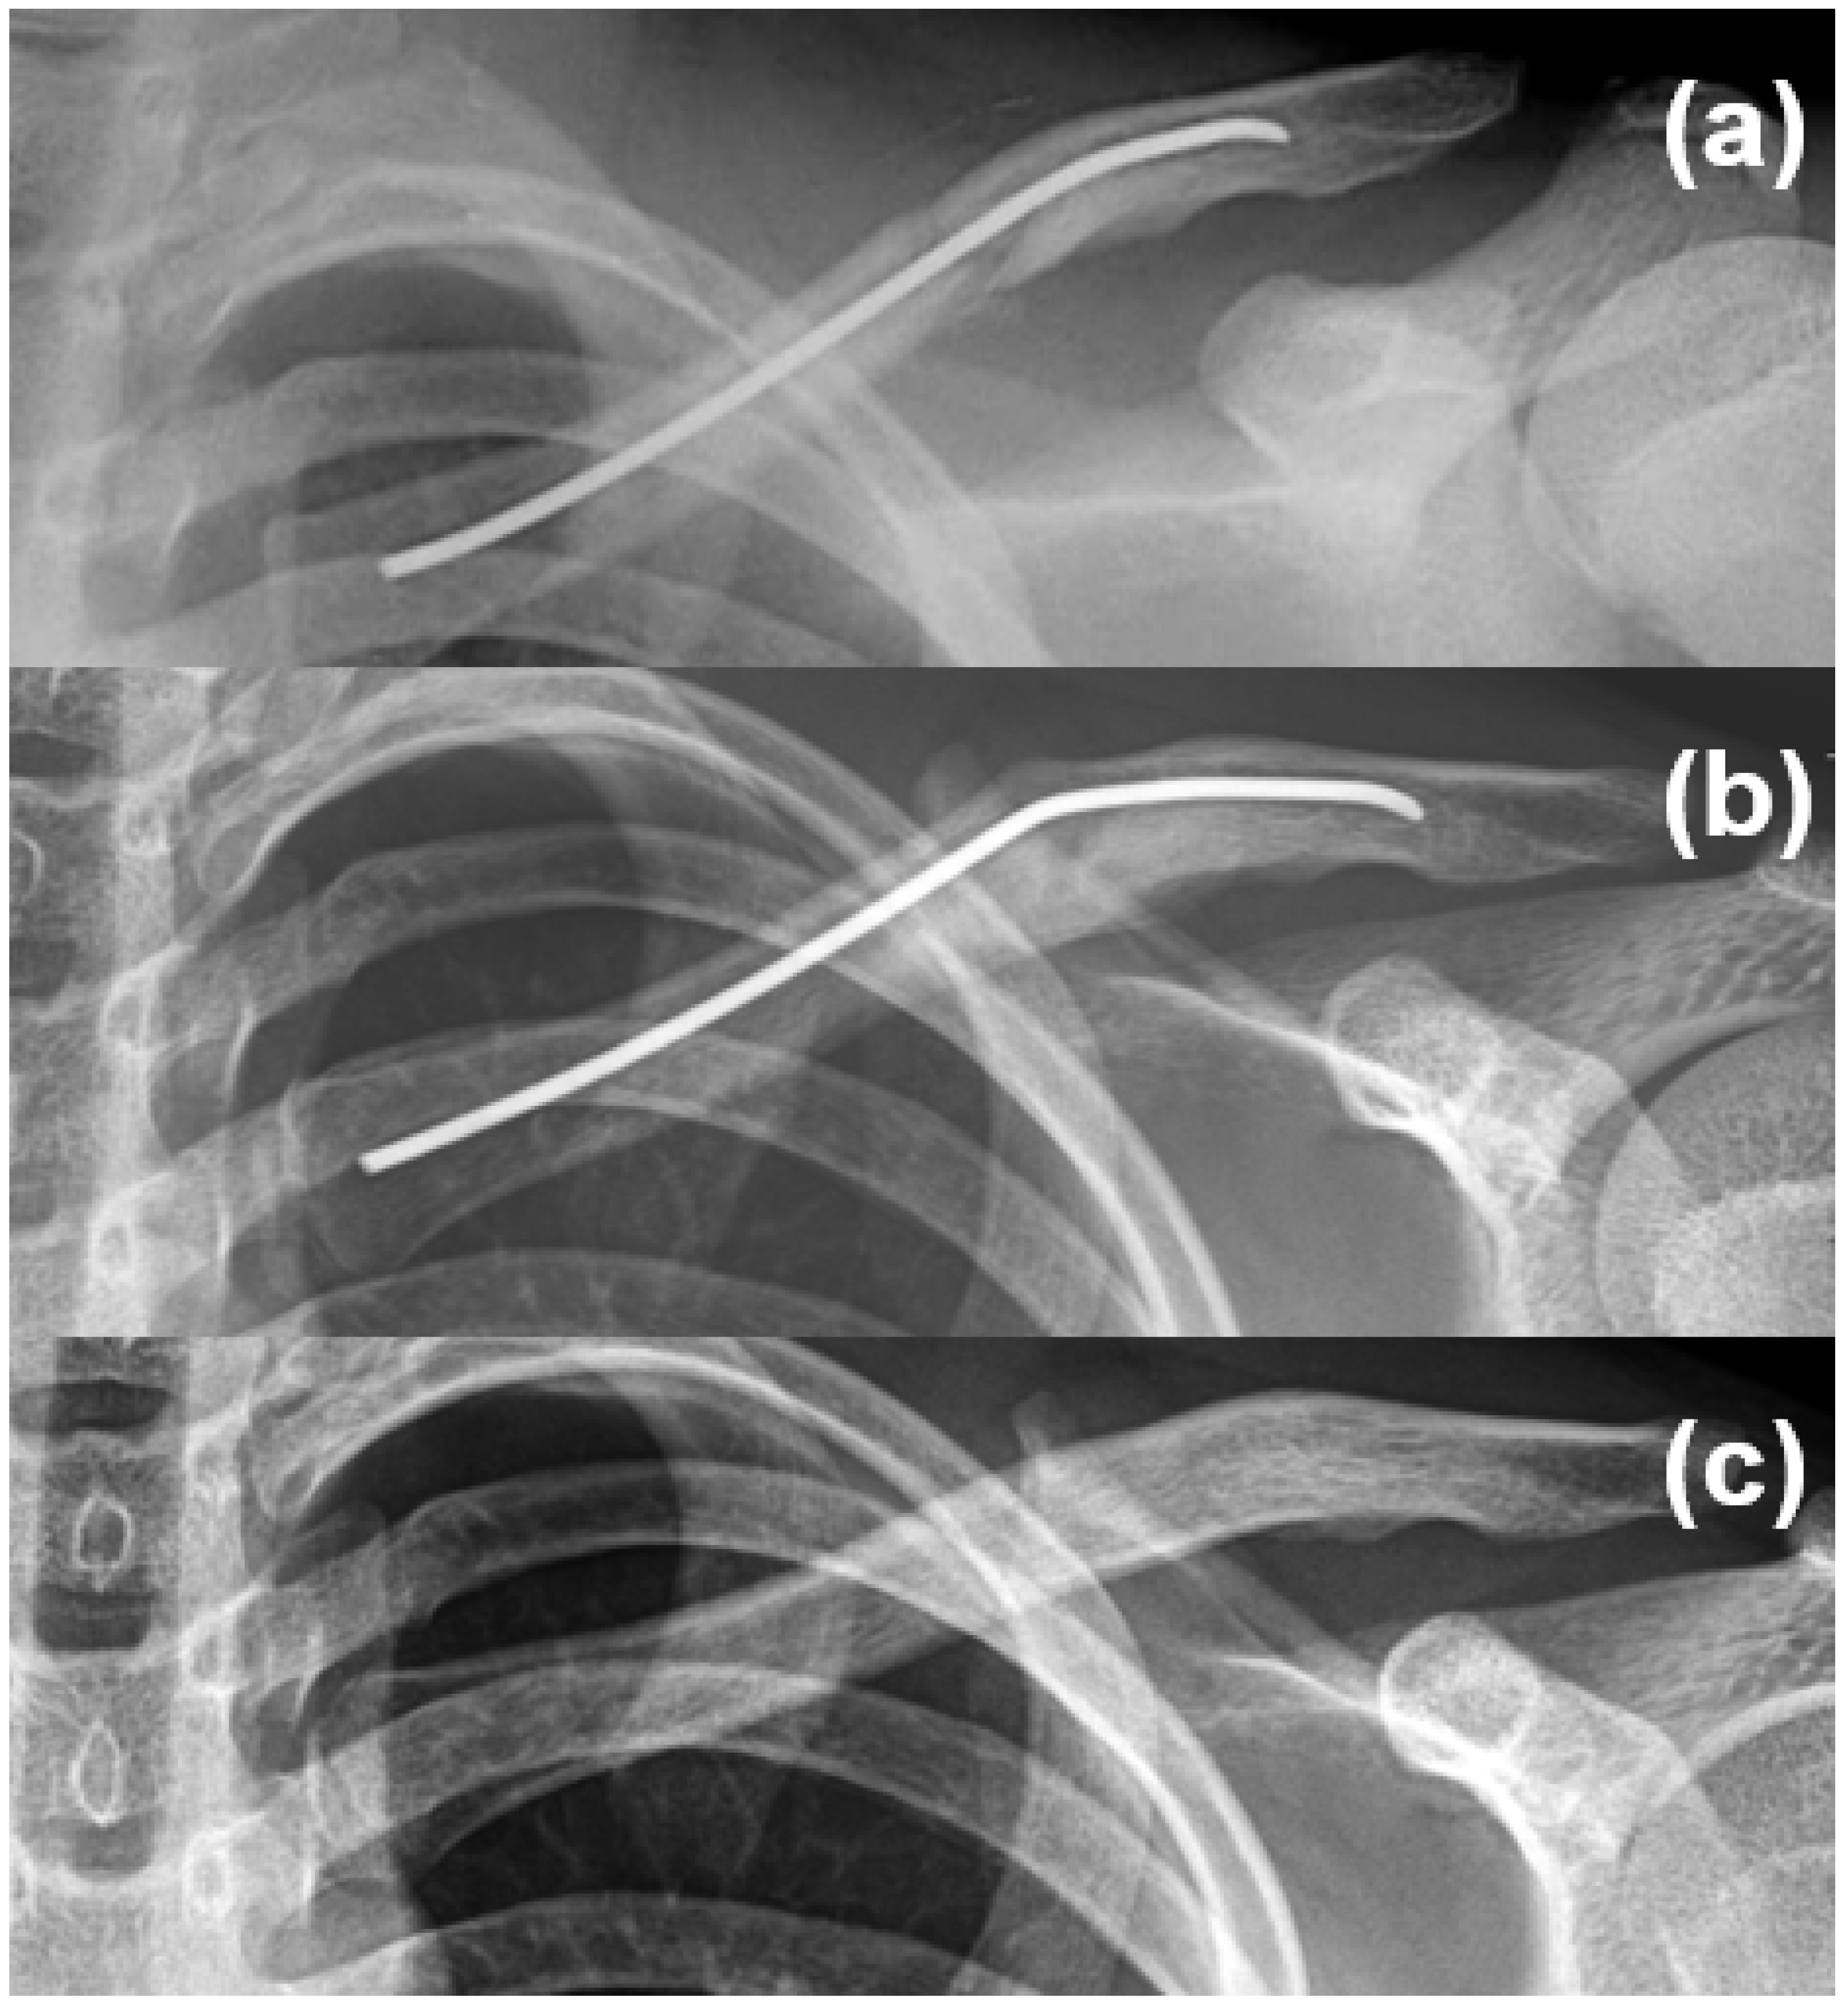

2.1. Operative Indications, Surgical Techniques, and Postoperative Management